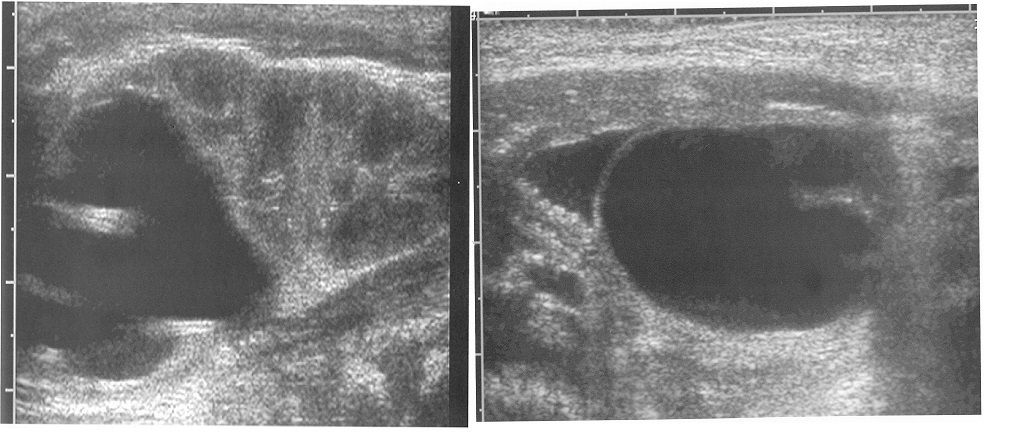

A one-month-old girl with prenatal hydronephrosis underwent postnatal imaging as shown. The most likely cause of findings in the bladder and kidney is:

Ureteral duplicaion is one of the most common renal abnormalities with approximately 1% of the population diagnosed as having a duplication anomaly during their lifetime with 10% of the affected indiiduals ill have a bilatral duplicatio anomaly. In individuals with a duplication anmaly, 10 Yo are diagnosed following an evaluation for a UTI, another 10% are discovered dnng an evluatio for p:enatal h.ydronephrosis , and the remainders are incidentally d1s ove:ed during rad1ograph1c evaluations. Severe upper pole hydronephrosis of a duplicated moiety 1s com?nly associated with either a ureterocele or ureteral ectopy, while lower pole hyronephros1s 1s common ly associated with vesicouretera l reflux or a UPJ obstruction. In this patient, the ulrasoud. (US) images are classic for obstruction of the upper pole due to a ureterocele. D1fferent1at1on of a ureterocele from an ectop ic ureter can at times be problematic. Indeed, te term “pseudourete:ocele” has been coined for enlarged ectopic ureter that protrudes into the bladder. Classically , a tip off that it is an ectopic ureter and not a ureterocele is found in the thickness of the ureterocele membrane. Presence of a thin-wall membrane is almost invariably associated with a ureterocele. In contrast, a thick-walled “ureterocele” or cystic structure may indicate a ectopic ureter with the thick wall being attenuated detrusor muscle. Inadvertent endoscopic incision of a pseudoureteroce le has led to the creation of detrusor-ureteral-vaginal f istulas that may be highly problematic to repair in a neonate. To differentiate. an ectoic uretr (pseudoureterocele) from a ureterocele, a VCUG may be helpful. If the ectopic reer insert into t.he bladder neck or urethra, reflux into the upper system may be faun? confirming the d1agnos1s of an ectopic ureter. If no reflux is noted and the physician has a high degree of suspicion that the diagnosis is truly an ectopic ureter, a pelvic MRI or CT scan may be of benefit.